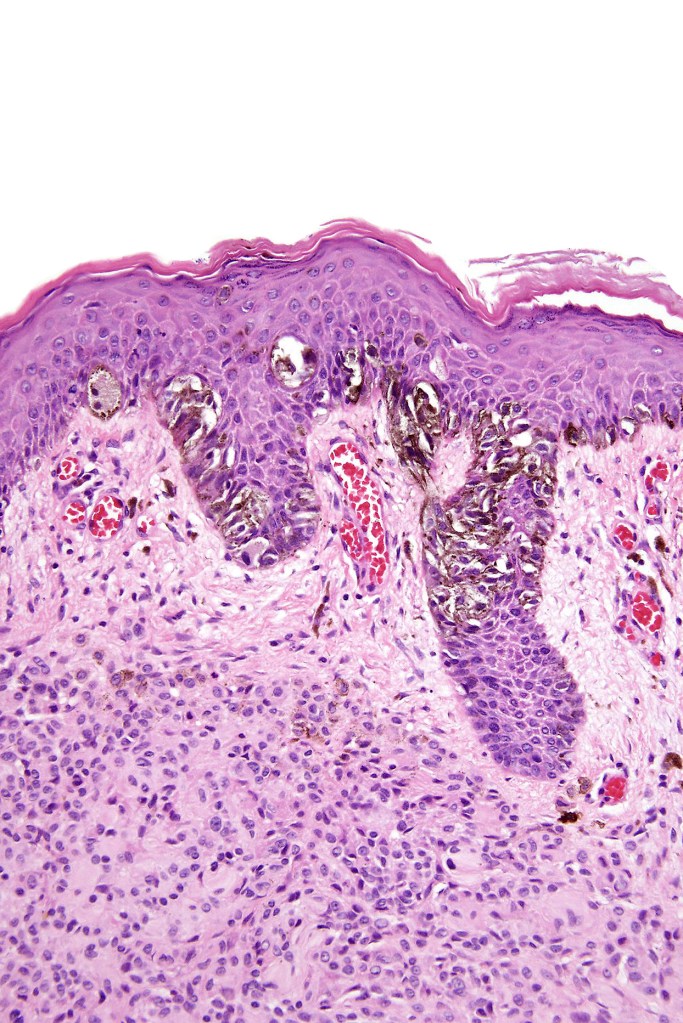

•Large dyscohesive nests with retraction artifact, not restricted to the tips of the epidermal ridges

•Heavy pigmentation (sometimes gray/green)

•Bridging common, often over multiple rete ridges

•Variable atypia (can be marked)